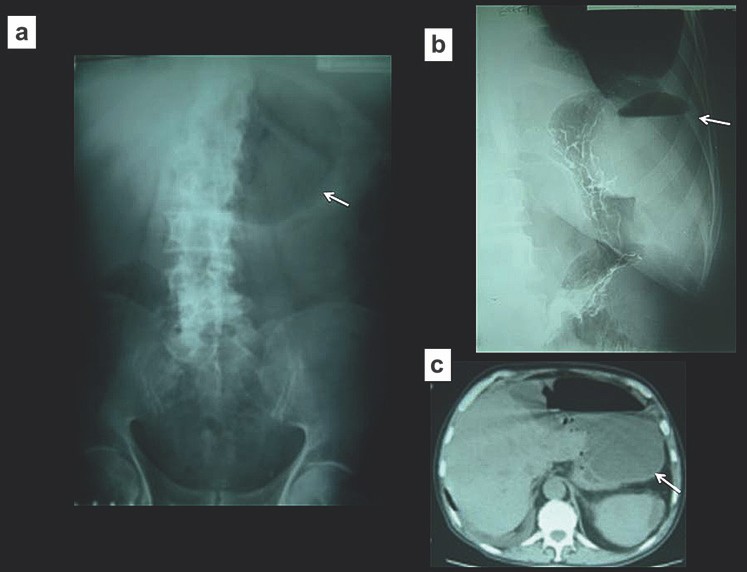

Tắc ruột do sỏi mật (gallstone ileus) gây khí trong đường mật. Hiện tượng này xảy ra khi một sỏi lớn bào mòn thành túi mật và rơi vào ruột non. Sỏi thường nằm ở đoạn cuối hồi tràng, gây tắc ruột non. Tam chứng X quang cổ điển trên phim X quang bụng thường quy là ruột non bị giãn, khí trong đường mật (pneumobilia) và sỏi mật vôi hóa.

Những đặc điểm trên chỉ thấy trong 50% các trường hợp (Hình 8). Tắc ruột do sỏi mật là một nguyên nhân quan trọng của tắc ruột non, nên cân nhắc tới nguyên nhân này đặc biệt ở những bệnh nhân nữ nhiều tuổi.

Hình 8. Tắc ruột do sỏi mật (a) Phim X quang bụng thấy khí ở trong hệ thống đường mật (b) Phim X quang cho thấy tắc tại vị trísỏi (c, d) Chụp CT xác định khí trong đường mật và sỏi mật gây tắc ở đoạn xa hỗng tràng.